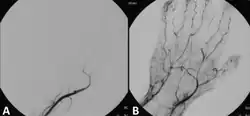

Angiograph before and after thrombolytic therapy in a case of acute limb ischemia.